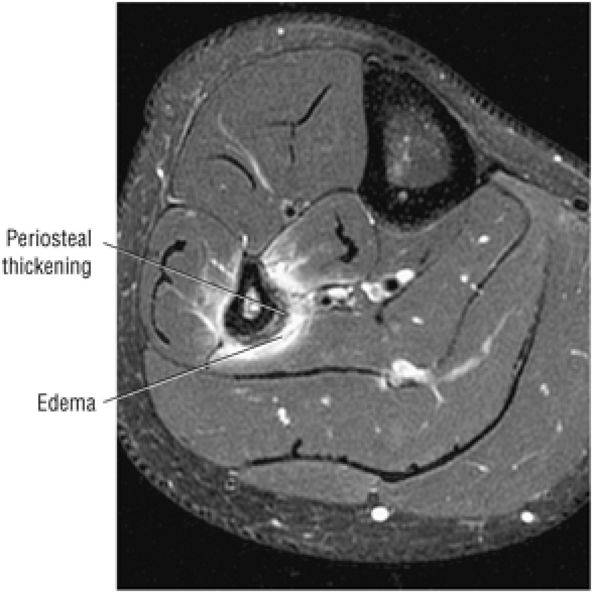

Stage I: Subchondral trabecular compression. Radiograph results are negative, bone scans are posi-tive, and marrow edema is seen on MR imaging (Fig. 5.95).

-